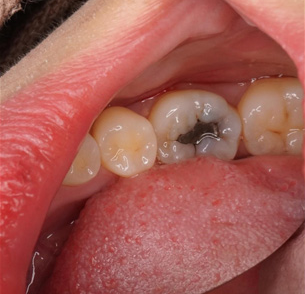

before

after

CASE 02

奥歯の虫歯の治療

• 施術概要

虫歯を確実に取り除いた後、食事でしっかり噛む力に耐えられる丈夫な素材(レジン)を丁寧に詰めて形を整えます。これにより、歯が本来持つ「噛む」という大切な機能の回復を図ります。ダイレクトボンディングを実施。

• 金額

33,000円(税込)

• 期間・回数

隣の歯との間を含まない虫歯治療の場合、治療回数は1回。 隣の歯との間を含む虫歯治療の場合、治療回数は2回。 虫歯が神経まで到達している場合は、2〜4回かかります。

• リスク・副作用

経年劣化によりレジンがすり減ったり着色し、将来的に再治療が必要となる場合があります。